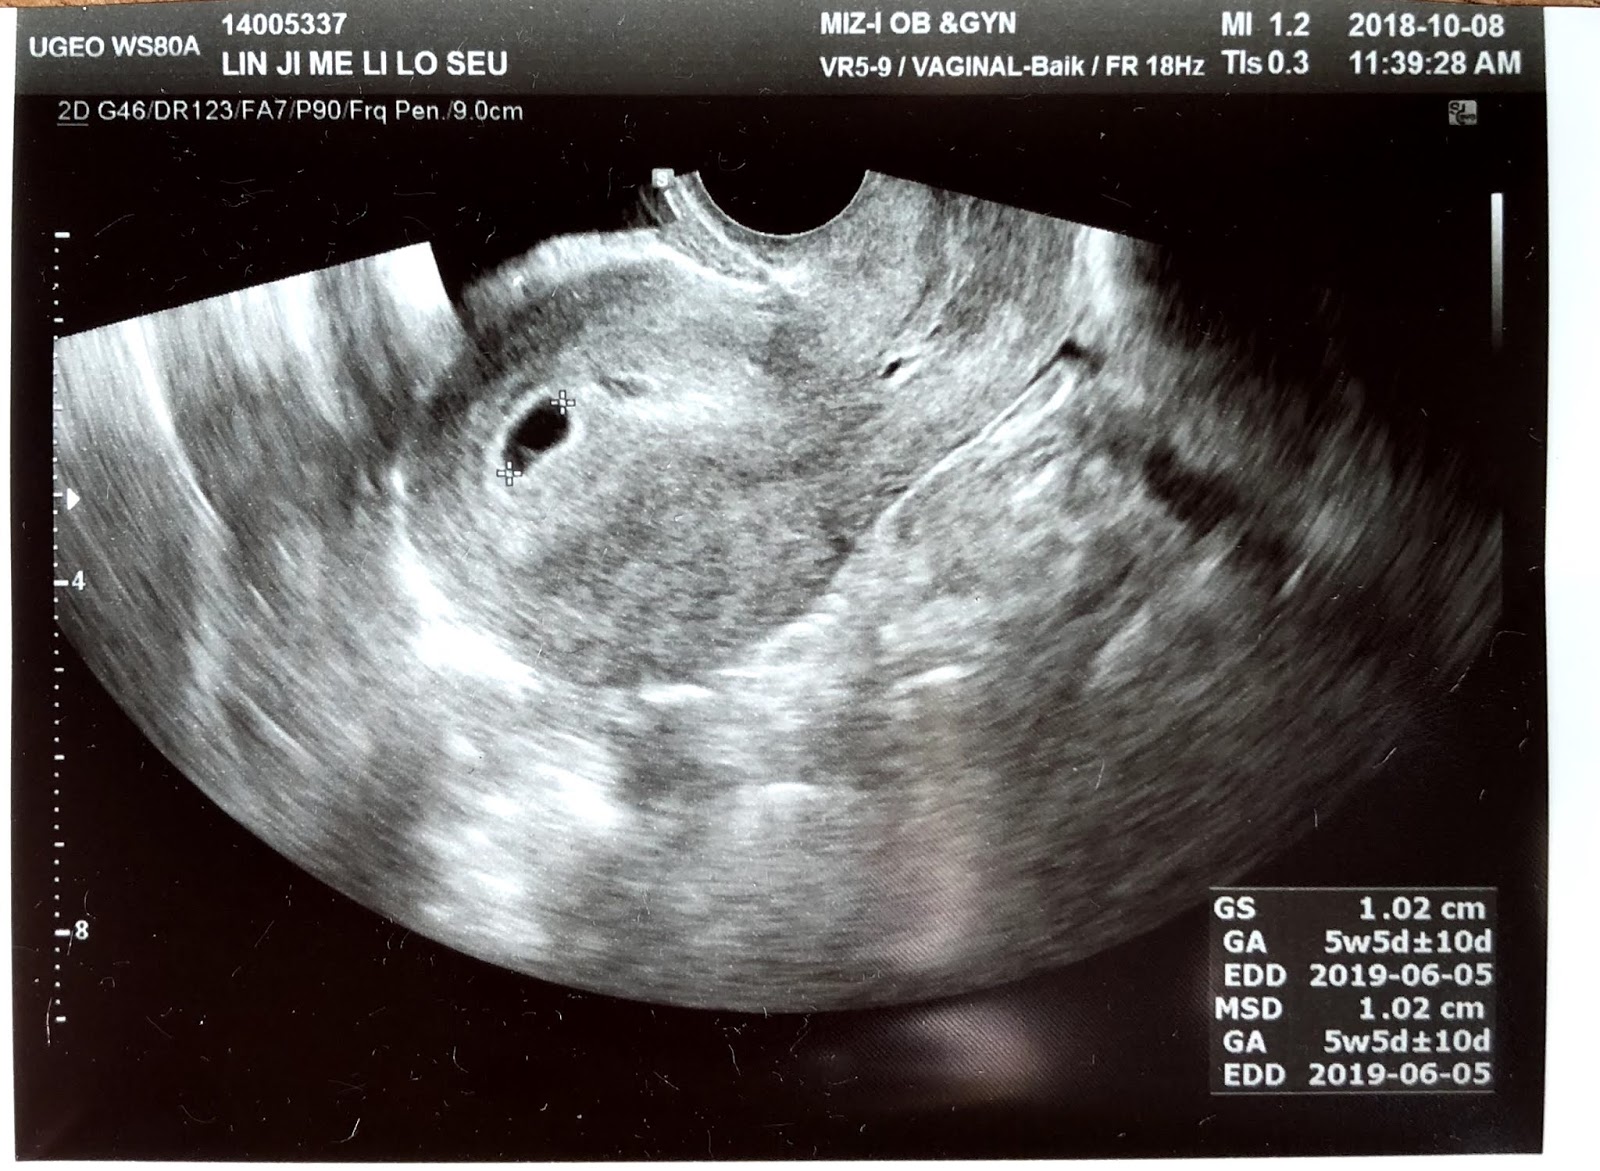

If you haven't yet heard, I'm pregnant! This sonogram was taken just as I was starting my 9th week -- look at those little legs!

Week 5 (first sonogram/confirmation of pregnancy; Hello, my name is Lin-ji Me-li Lo-seu)